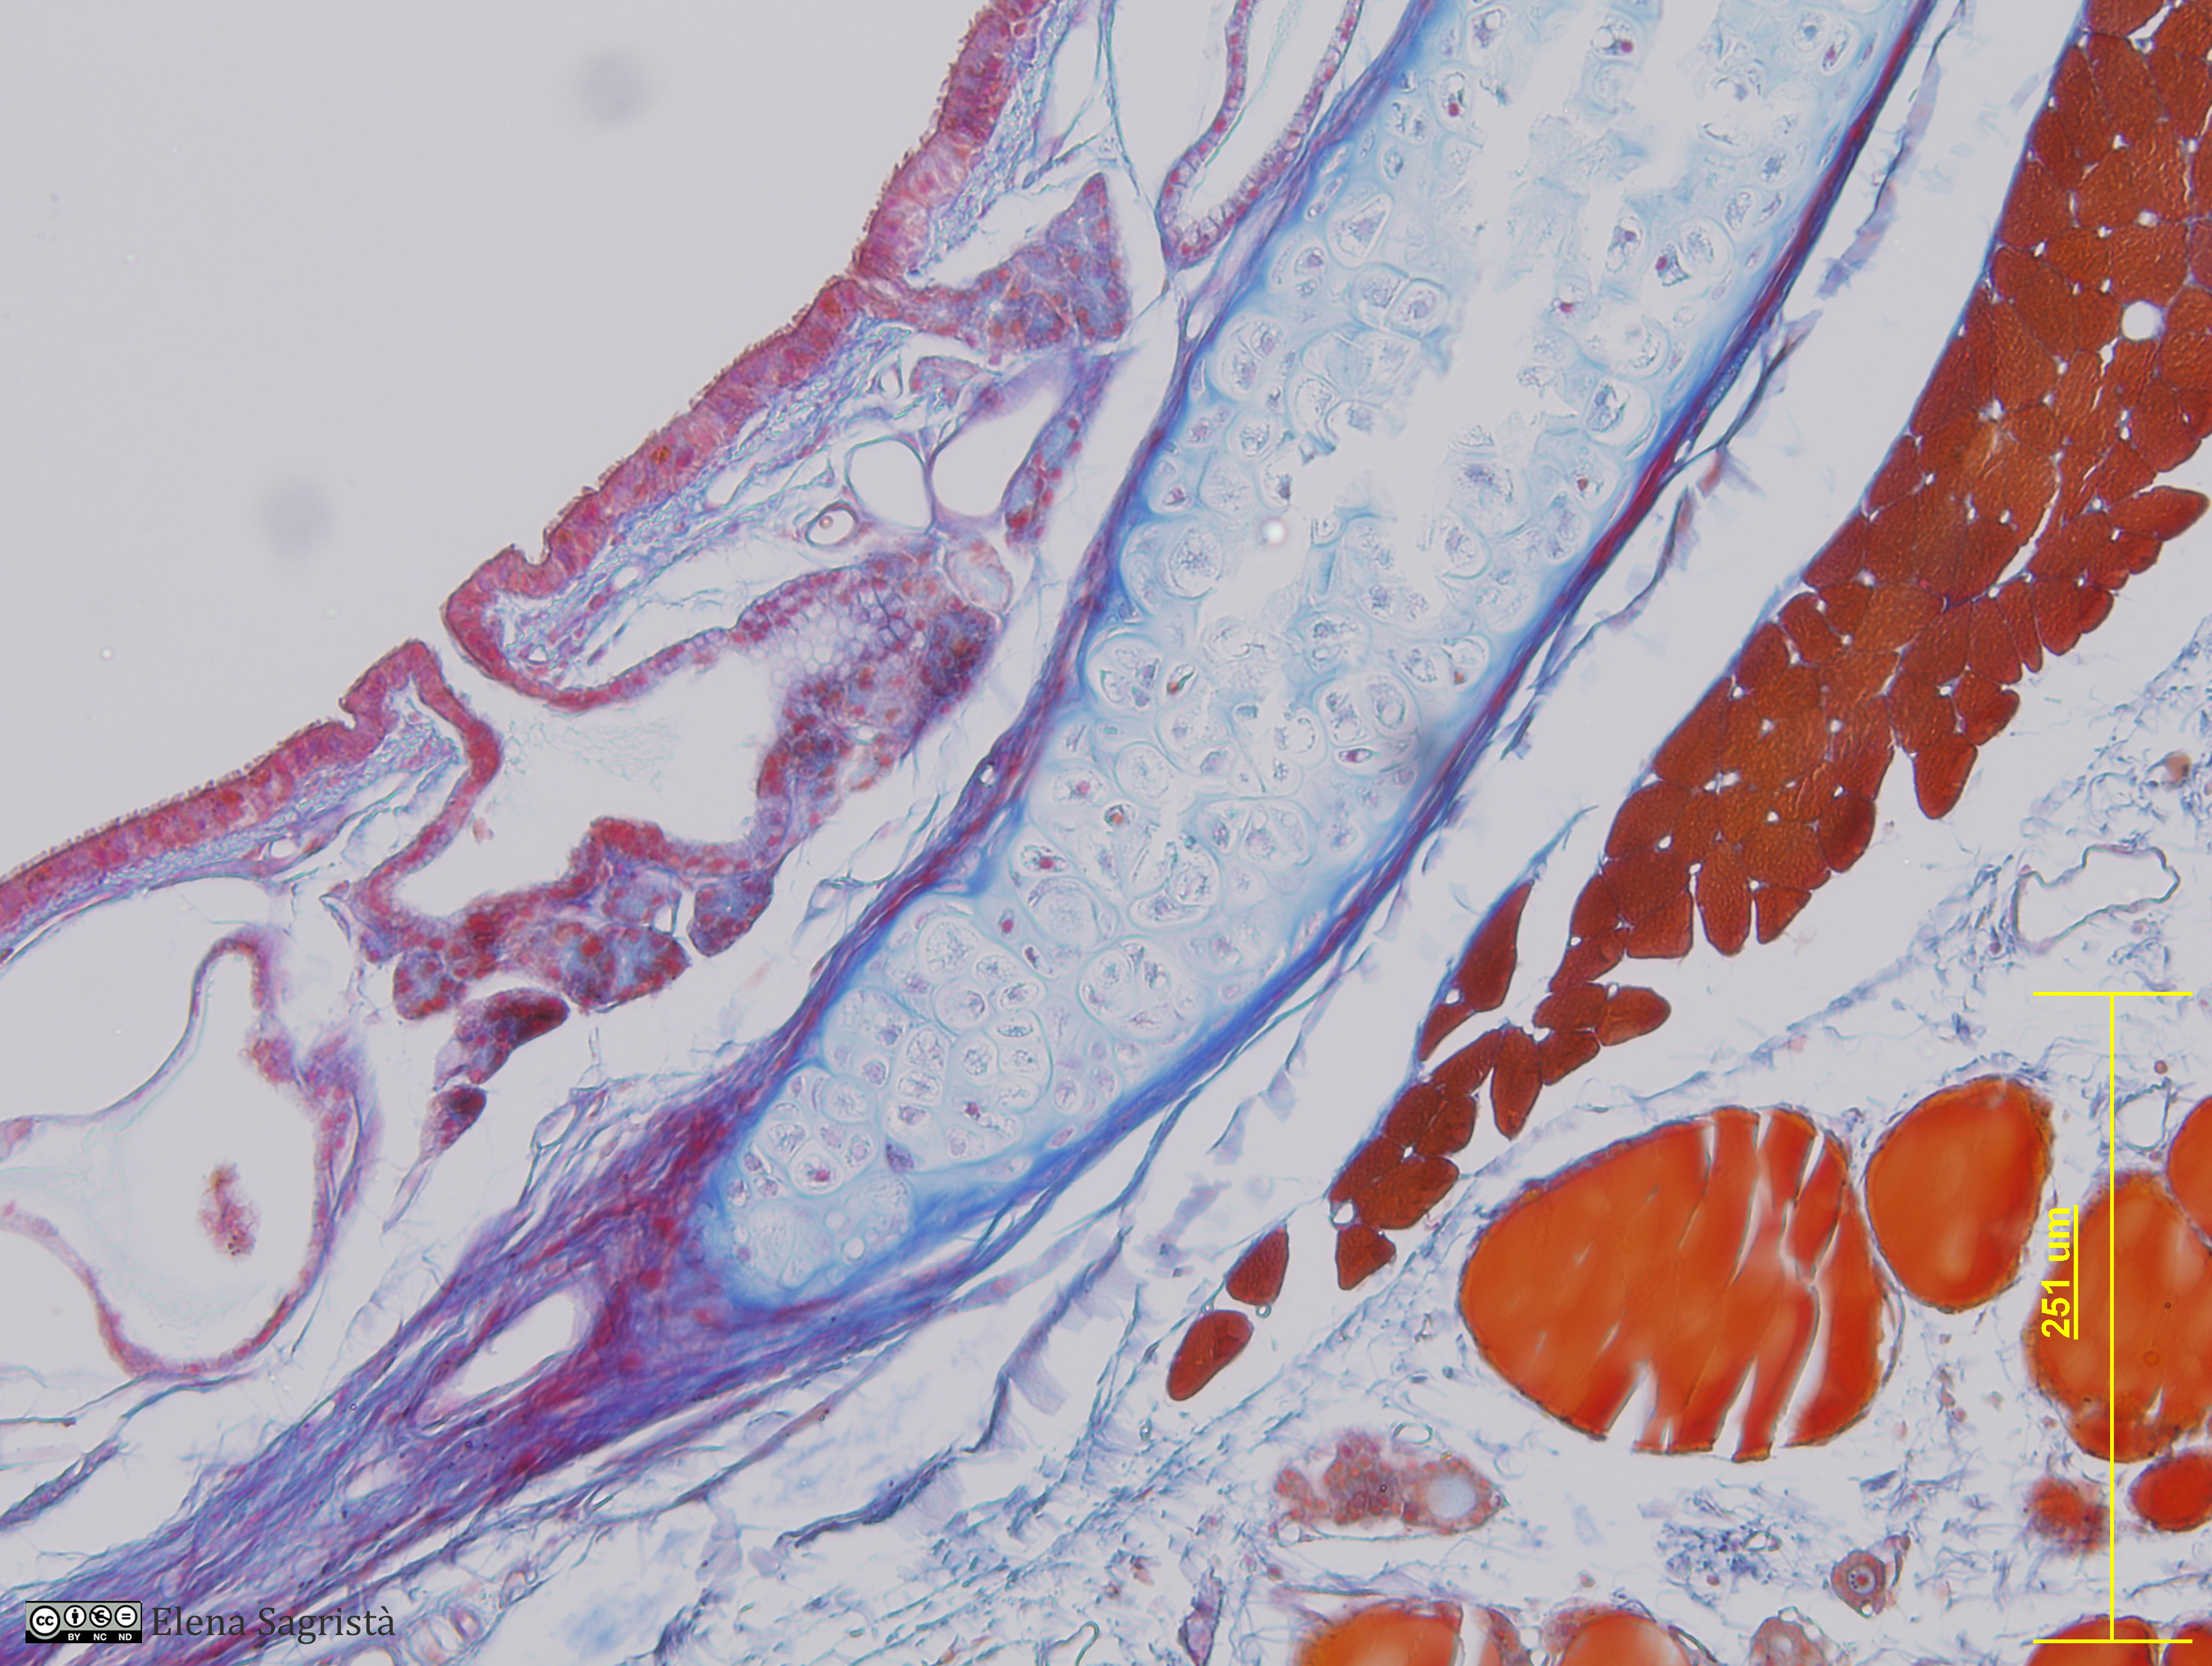

Histologia imatges: 12 Tràquea

Imatges de preparacions histològiques de Tràquea. Microscopia òptica.